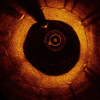

May 15, 2020 – A late-breaking study aimed to evaluate whether optical coherence tomography (OCT) can predict…